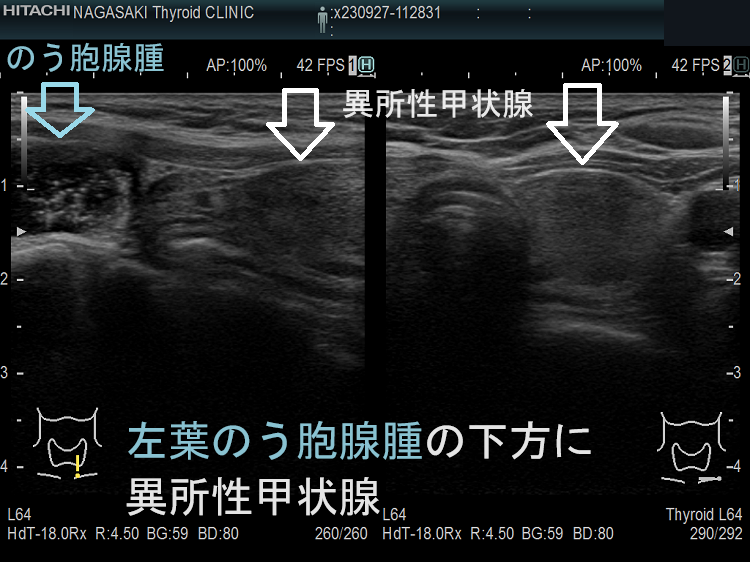

のう胞腺腫の下方にある頚部異所性甲状腺(非腫瘍)

左葉のう胞腺腫の下方に異所性甲状腺(非腫瘍)

左葉のう胞腺腫の下方にある頚部異所性甲状腺(非腫瘍):下極の副甲状腺と同じ位置。甲状腺本体と同様の組織です。

左葉のう胞腺腫の下方にある頚部異所性甲状腺(非腫瘍)

頚部異所性甲状腺(非腫瘍)の上にある左葉のう胞腺腫